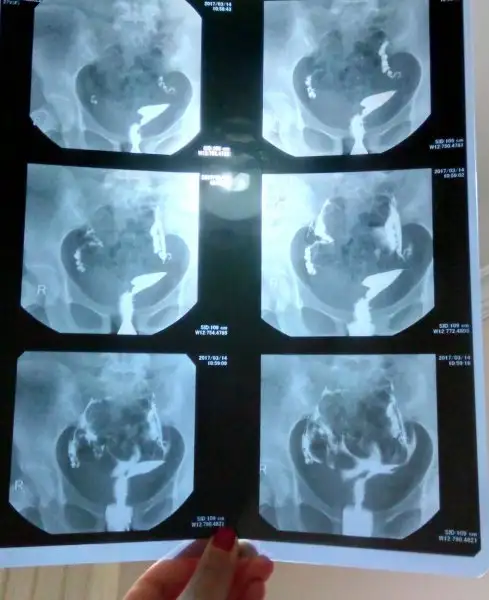

Bana niye laparoskopi önerdiler anlamadım geçiş var ama karın boşluğuns yayılmadi sıvı ondan sanırım rahim filmi röntgeni ne bakabilirmiyim

D dilekkk84 buraya atiyorum canim.. kizlar sizler de bir bakar mısınız anlayan varsa kendisininkiyle benimki nasil diye?tuplerde bir sorun goren var mi